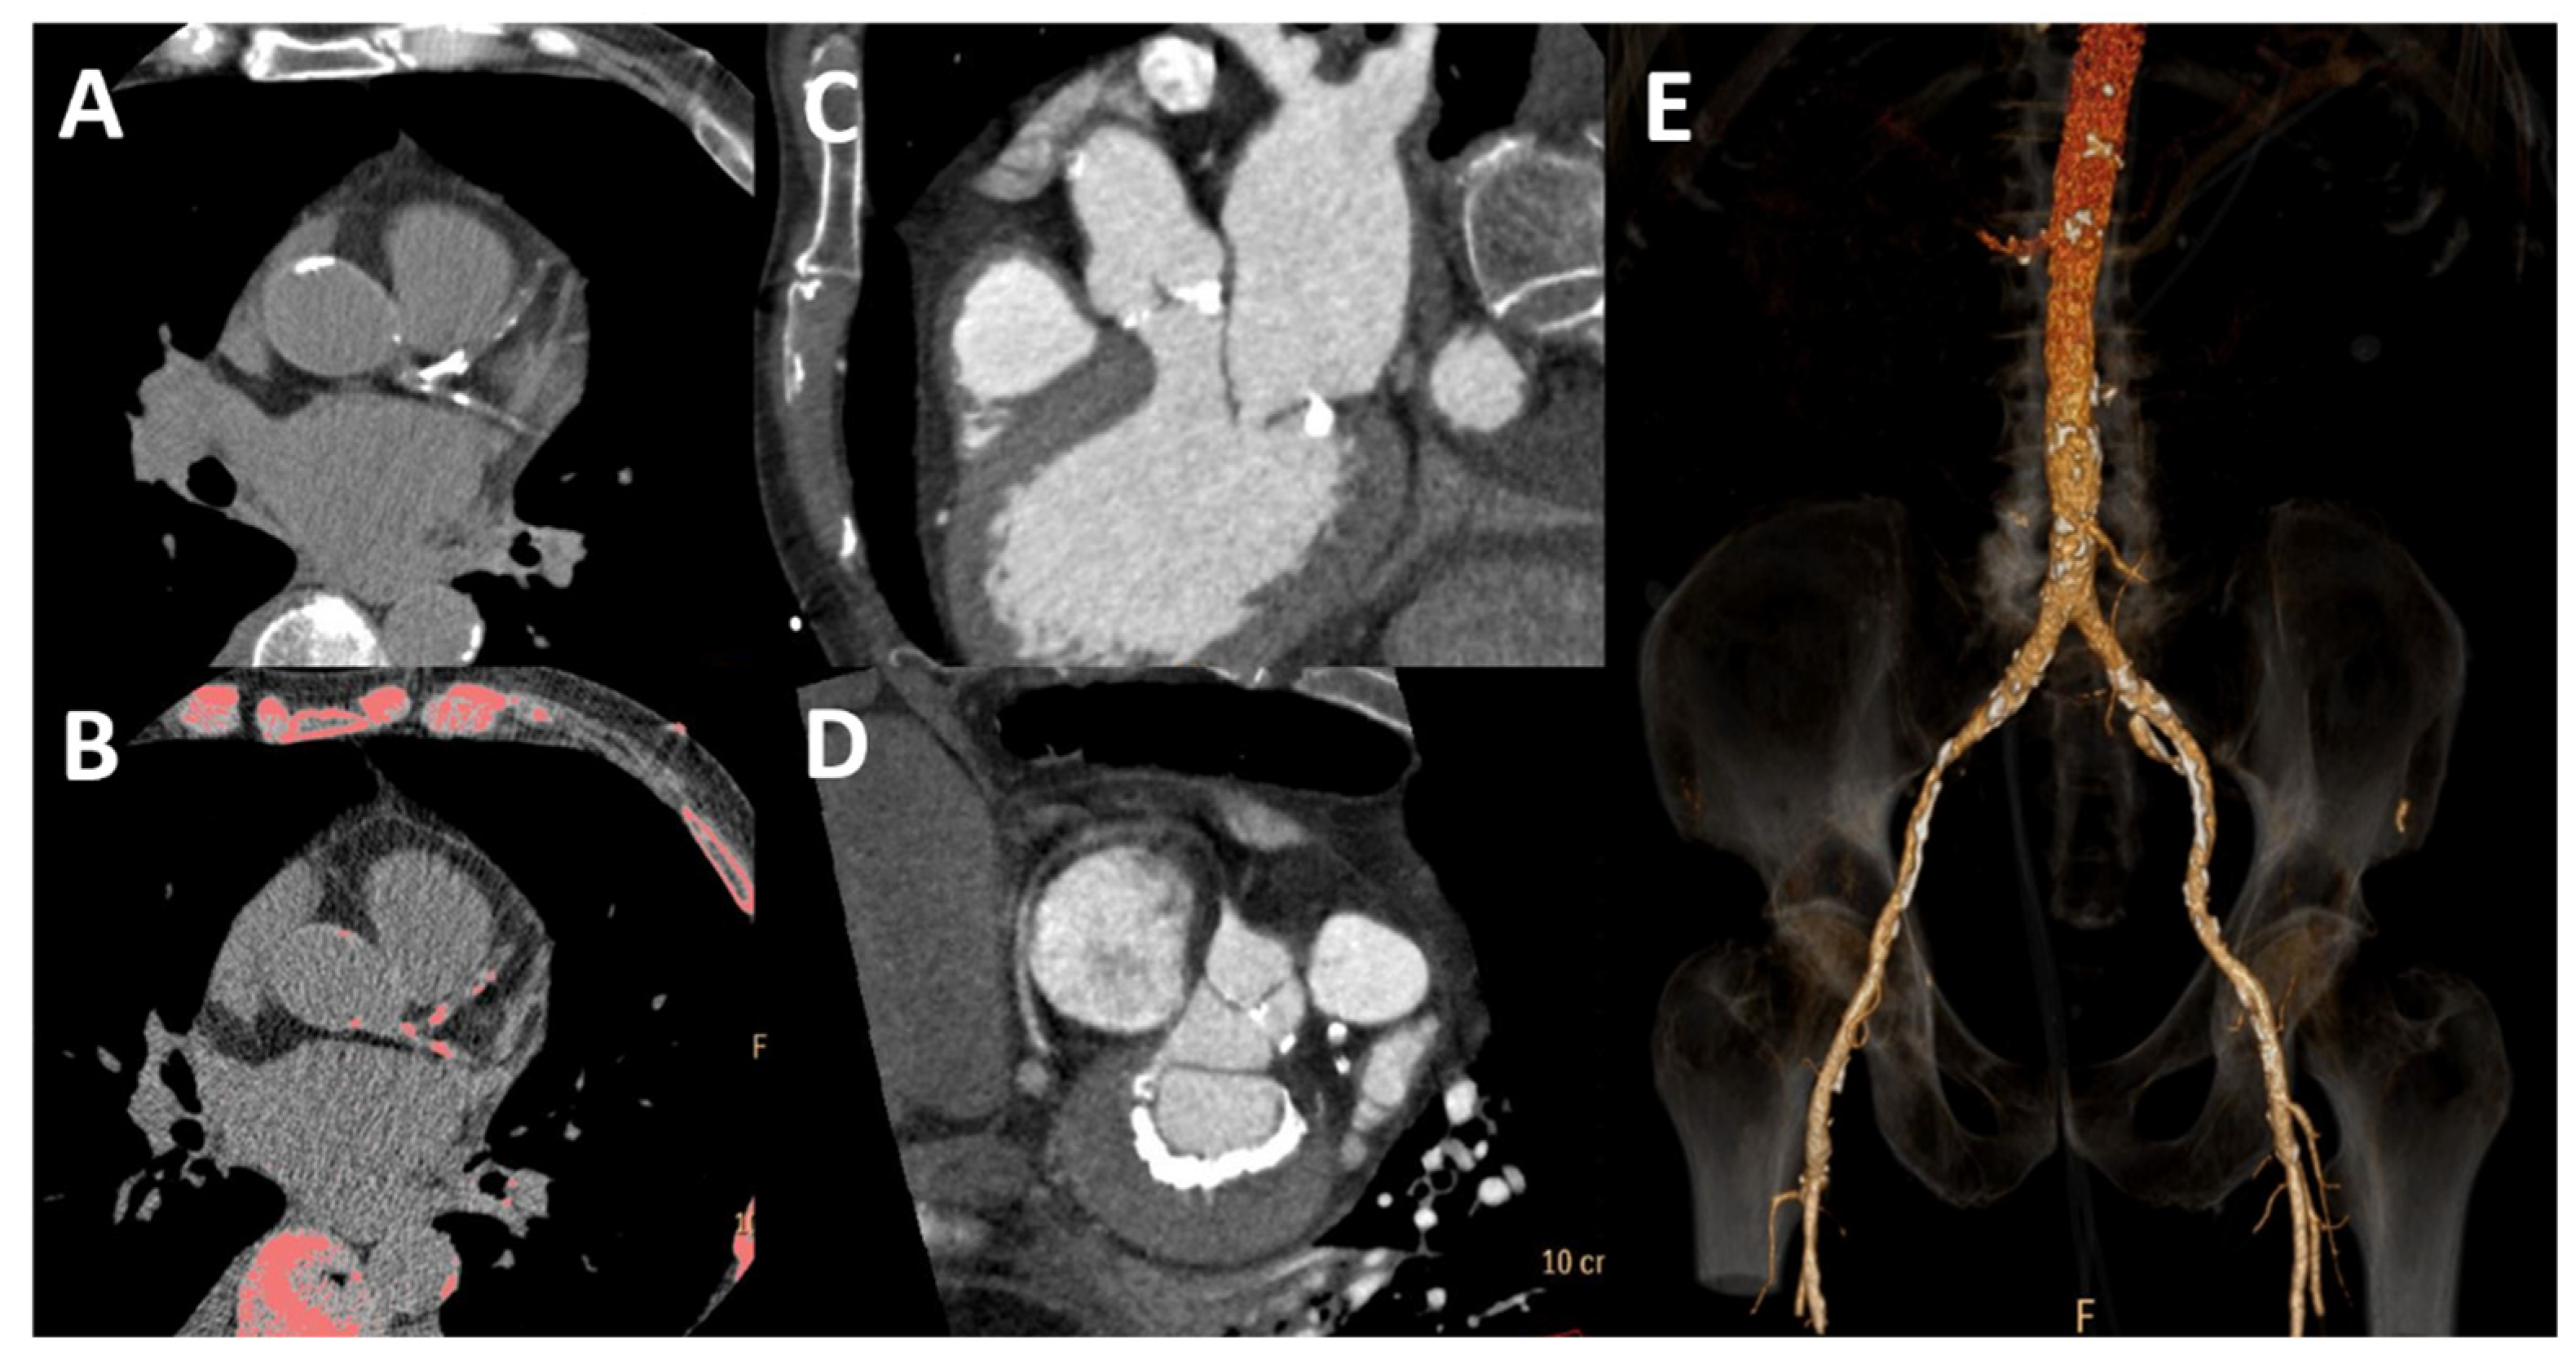

CKD presents with common and extensive arterial and valvular calcification (Figure 4) due to a pronounced impairment in bone and mineral metabolism, which is easily seen by CT. A disproportionate amount of coronary, aortic and mitral calcium is a well-known finding in patients with ESRD undergoing dialysis [56]. However, even among young dialysis patients (20–30 years old) with otherwise low CV risk, calcification is common and significant; even more importantly, this calcification is rapidly progressive [57]. However, data on coronary artery disease in the earlier stages are more limited. A population study found an association with significant coronary calcification, which was directly related to the stage of renal dysfunction, with no relevant calcification in stages 1–2 compared to a population with no CKD; this association was notably stronger among diabetics [58]. Coronary calcification, quantified by Agatston calcium score (Figure 4A,B), retains prognostic significance in this setting, as outlined by multiple studies [59,60,61]. Calcification of the aortic wall is frequently observed as well. This is associated not only with increased vascular stiffness, as expected, but also with higher degrees of diastolic dysfunction [62], marking a more advanced stage of disease with worse prognosis [63].

Figure 4.

Cardiac and vascular calcification by computed tomography. Coronary calcification is present in bright white (A) and pink after post-processing (B). There is calcification of the aortic valve (C) and posterior mitral anulus (D) and vascular calcification of the abdominal aorta and iliac arteries (E).